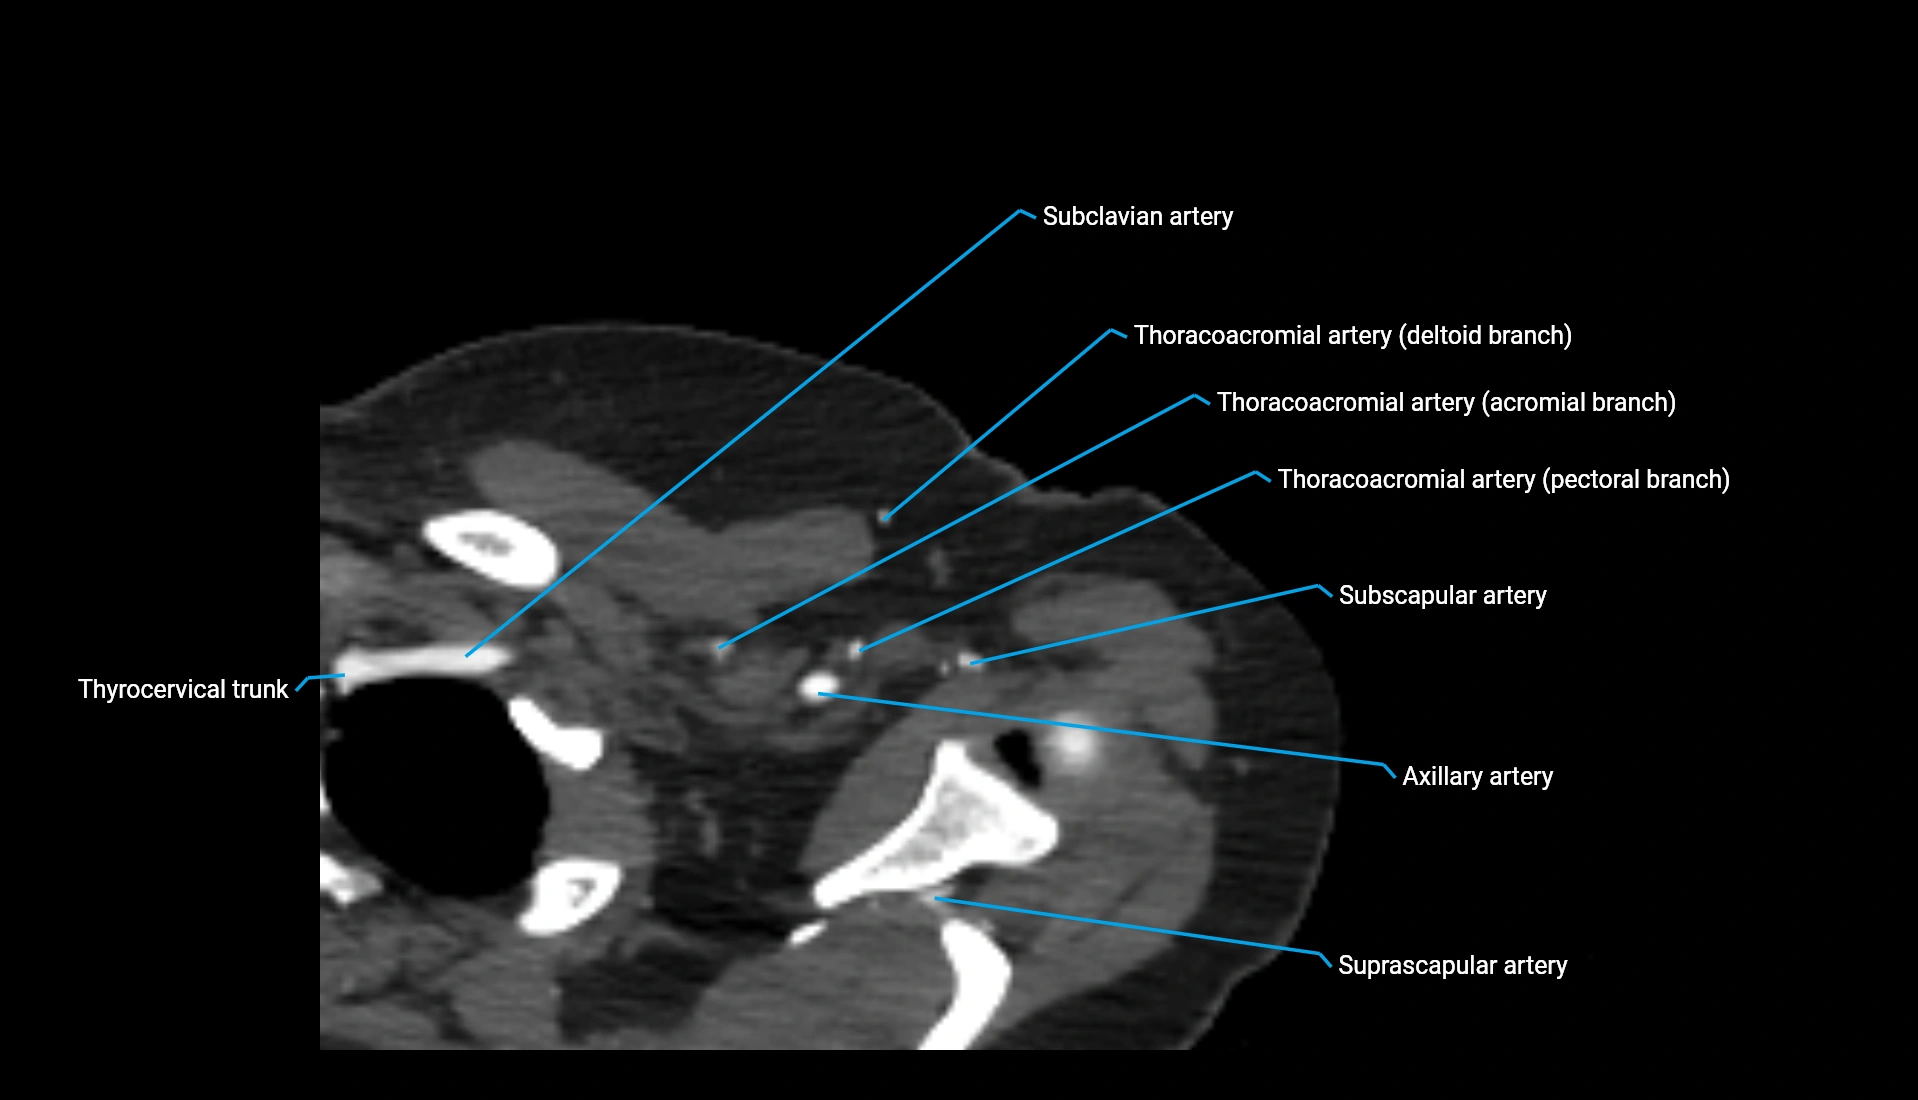

CT Appearance

Non-Contrast CT:

• Cortex: High-density, sharply defined

• Subchondral bone: Dense cancellous matrix

• Articular surface: Smooth concave contour articulating with the capitellum

• Excellent for evaluating bone integrity, alignment, and subtle fractures

Post-Contrast CT:

• Bone: No enhancement

• Joint capsule and synovium: Mild enhancement outlining the joint

• Improves contrast between soft tissues and bony margins

• Useful in detecting subtle joint abnormalities or postoperative changes